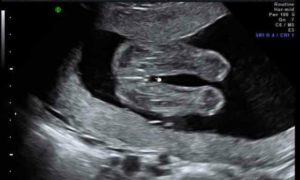

Можно ли на 16 неделе беременности узнать пол ребенка

Страстное желание узнать пол малыша на первых месяцах беременности неискоренимо. Родители высчитывают время зачатия, изучают глянцевые журналы и гадают на кофейной гуще. Родственники добавляют жару – прогнозируют девочку или мальчика и отстаивают свою точку зрения до последнего, даже если специалист четко увидел пол ребенка на обследовании.

Мы попробуем прояснить, на какой неделе (месяце) беременности результативно УЗИ, какие способы и приметы пригодятся, чтобы узнать будет ли это мальчик или девочка.

Точно ли УЗИ определит пол ребенка?

Безусловно, самым точным методом определения пола будущего любимого чада является УЗИ.

Проблема лишь в том, что УЗИ можно проводить на определенных сроках беременности, не более трех раз (на 13-й неделе, на 23-24 неделе, непосредственно перед родами).

Вывод: УЗИ – самый точный метод, но он тоже дает осечку. Срок беременности, развитие малыша, уровень специалиста, точность оборудования, положение ребенка в животике на момент проведения исследования – все эти важные факторы могут повлиять на результат.

Важно! Гениталии малыша формируются на 11-й неделе. Но в самом начале формирования пениса у мальчика это скорее небольшой бугорок, чем полноценный орган, который легко заметить.

Только к 13-й неделе он вытягивается в длину и становится более осязаемым. На раннем этапе их развитие настолько незначительно, что перепутать пол ребенка очень легко.

Специалист даже очень высокого уровня может предположить, кто родится, но гарантировать результат не сможет.

Срок беременности – важный показатель

К 19 неделе хороший специалист уже сможет на 80% быть уверенным в том, кто у мамы в животике: мальчик или девочка. Мальчика определить проще, а если вы ожидаете девчушку, то лучше обратиться к узисту уже на 24-й неделе беременности.